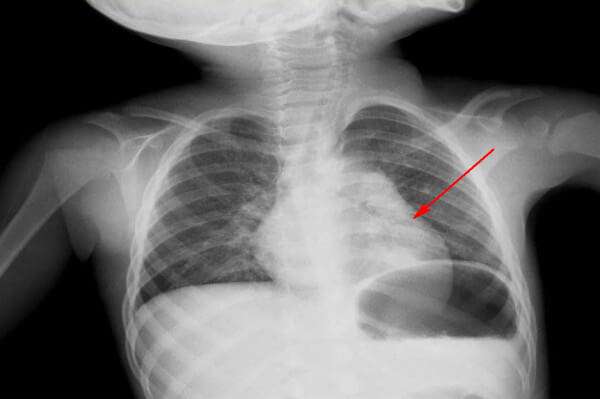

Острая пневмония имеет инфекционный характер развития. При заражении в легких начинается острый воспалительный процесс, сопровождающийся синдромом интоксикации и респираторной недостаточностью (дыхательная недостаточность). У пораженного ребенка появляются местные хрипы и укорачивается звук перкуссии. Альвеолы заполнены экссудатом (жидкостью).

По морфологическим формам медики выделяют еще одну классификацию. Это очаговая, сегментарная, церебральная и интерстициальная пневмония. Эти типы различаются степенью поражения и поражения сегментов легочной ткани.